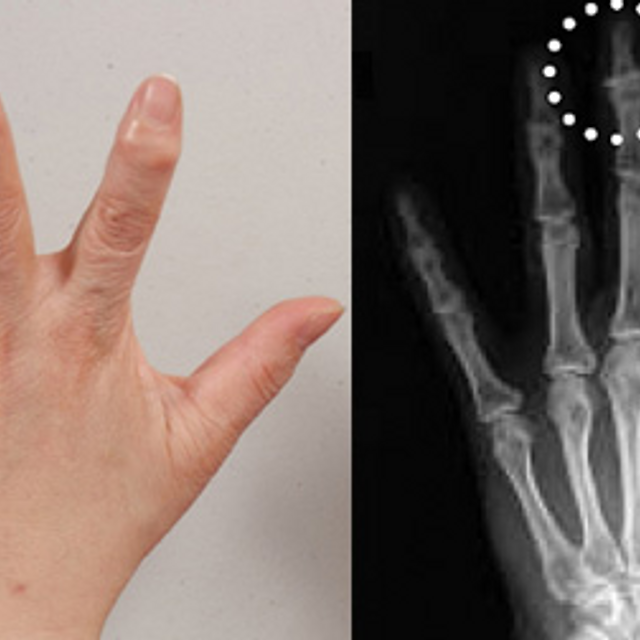

| 손가락 관절염인가? 손가락 마디가 붓고 아플 때 (0) | 2017.02.06 |